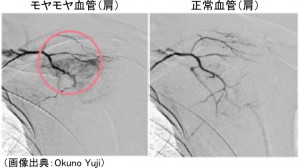

の2種類があり、モヤモヤ血管とは病的血管のことです。モヤモヤ血管発見者の奥野氏に聞いたわけではないですが、見た目がモヤモヤとしているため「モヤモヤ血管」と分かりやすくネーミングしたと思われます。

こちらの画像の方が分かりやすいかもしれません。

このように、モヤモヤした(ぐちゃぐちゃした)血管が、肩こりなどの慢性痛の場所には存在するのですが、モヤモヤ血管はレントゲンやMRIには映らないため、今まで気付かず検査されてこなかったのです。